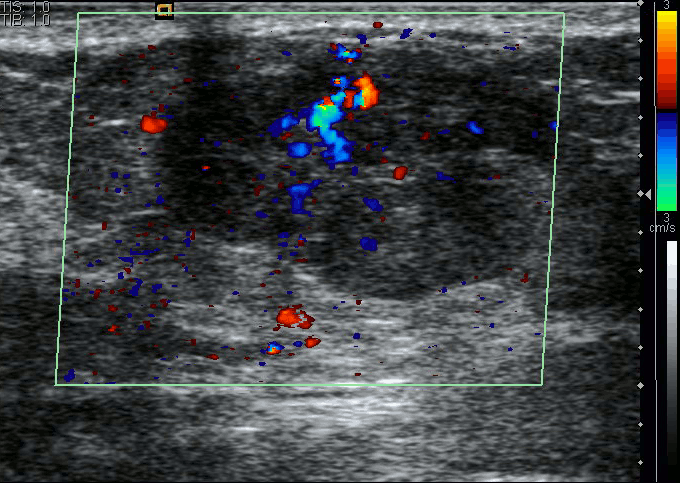

乳腺超声

亚洲女性的乳腺密度相对致密,对于致密型乳腺,超声相较于乳腺X线有较高的敏感性,且对人体没有辐射伤害。 因此在中国,大多体检会偏向于使用 超声。中国也是目前世界范围内乳腺癌超声数据最为丰富的国家。”

当然通过这种方式,医生仅能得出一个良/恶的初步判断, 对于乳腺癌的分子亚型,人眼是无法察觉的。

乳腺癌超声图像预测

而作为对比,SonoBreast,只需要将一张超声图片输入,便可以在几秒钟之内获得分子亚型的分类结果。目前,研究团队已经发布了Web端接口( open.baai.ac.cn/sonobreast ),任何人都可以上传超声图像,从而获得一个可借鉴的预测结果,这个结果包含了对每种亚型的预测置信度。